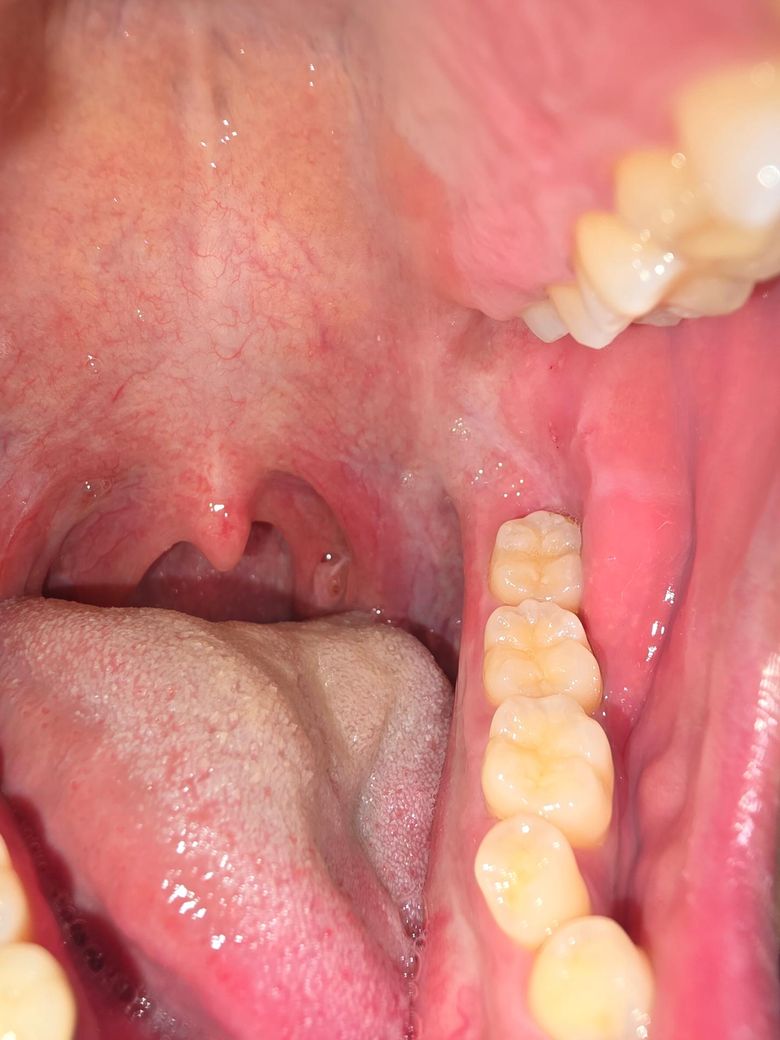

왼쪽 편도에 작은 빨간 점이 생겼습니다.

최근에 편도결석같은 이물질도 나오고 좀 아파서 봤더니 작은 붉은점에 가운데가 하얗습니다. 편도염인가요 궁금합니다. 따로 열나거나 하지는않지만 가렵기도하고 그럽니다.

• 2번 째 사진

올려주신 사진만으로는 다소 제한적이나 편도염을 추정할 수 있는 편도 비대나 염증 소견은 뚜렷하지 않으므로 음주, 흡연, 카페인, 자극적 음식을 피하고 경과를 지켜보기 바랍니다.